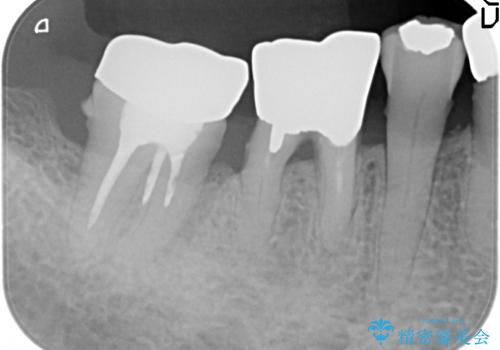

歯ぐきから血が出る、歯ぐきが腫れている 80代女性

- 歯ぐきからの出血と腫れを主訴に来院された患者様です。

プラークコントロールが非常に悪く、全顎的な歯周病に罹患していました。

「抜歯したくない、インプラントは嫌」という患者様のご希望とご年齢を考慮し、可及的な骨外科処置や根分割術によりできるだけ今ある歯を残す治療方針をたてました。

保存不可能な左上の奥歯2本(左上67)は抜去し、ノンクラスプデンチャーをいれることにしました。

長期的な予後は保証できないことをご了承頂いた上で治療を行いました。

ご希望により、積極的な再根管治療は行いませんでした。